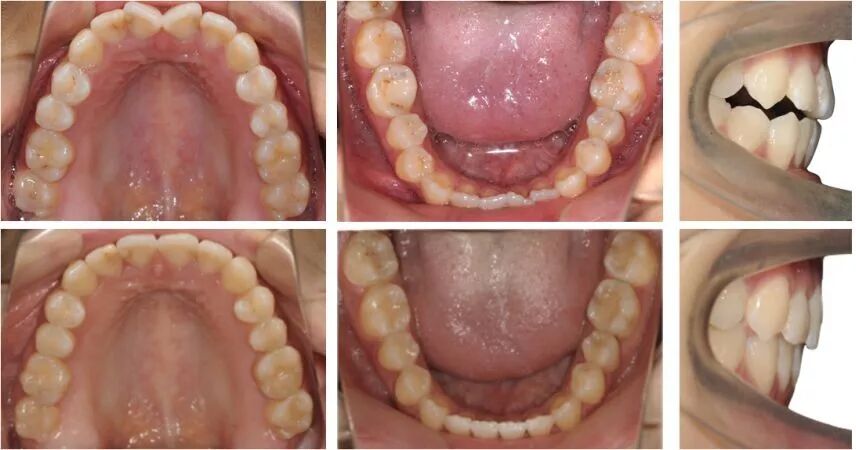

保持中:

患者保持3个月的面像

保持3个月的口内像,可以看到矫治效果是比较稳定的。

治疗后头影重叠图可见47牙大量前移关闭拔牙间隙,下颌前上旋转;下前牙少量伸长解决开合,下前牙少量内收、直立。